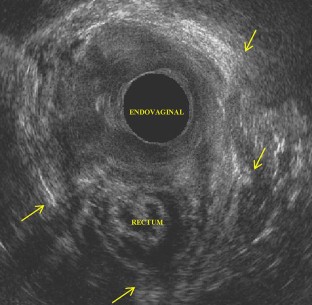

A cross-sectional study was conducted in a in tertiary maternity. All primiparous women with vaginal deliveries that occurred between January 2013 and December 2015 were invited. Women who attended the invitation underwent detailed anamnesis, questionnaire application, physical examination and endovaginal and endoanal 3DUS. Crude and adjusted predictor factors for PFD were analyzed.

Fig. 1

Fig. 2